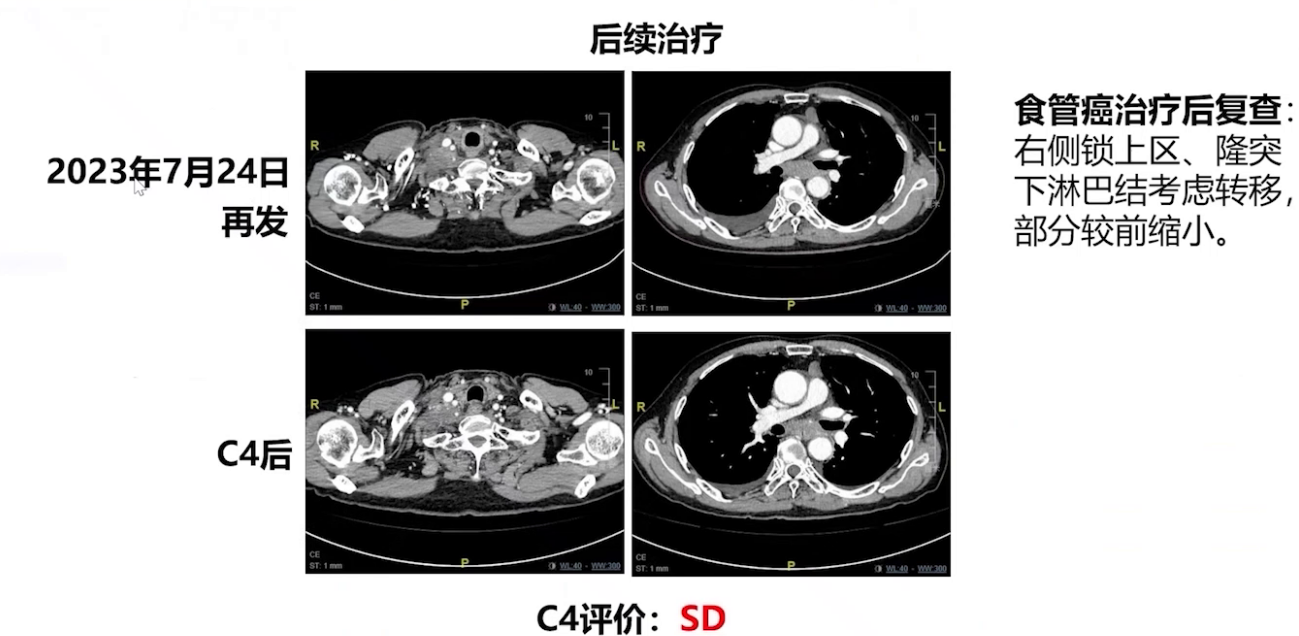

3、2022年9月患者出现隆突下淋巴结增大,考虑PD ,10月行局部放疗,后进入观察期。今年7月复查CT,右侧锁骨上区及隆突下淋巴结再次增大,评估为病情进展。鉴于既往一线方案疗效显著,采用白蛋白紫杉醇联合奈达铂方案治疗,完成4周期化疗,病灶控制良好,疗效评价SD 。